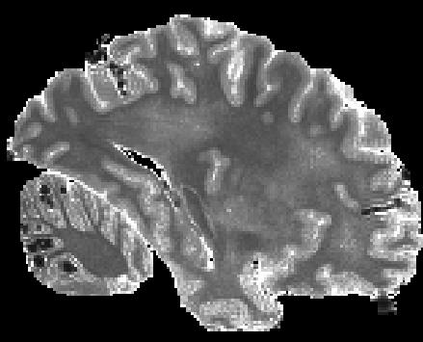

In neuroimaging, MRI tissue properties characterize underlying neurobiology, provide quantitative biomarkers for neurological disease detection and analysis, and can be used to synthesize arbitrary MRI contrasts. Estimating tissue properties from a single scan session using a protocol available on all clinical scanners promises to reduce scan time and cost, enable quantitative analysis in routine clinical scans and provide scan-independent biomarkers of disease. However, existing tissue properties estimation methods - most often $\mathbf{T_1}$ relaxation, $\mathbf{T_2^*}$ relaxation, and proton density ($\mathbf{PD}$) - require data from multiple scan sessions and cannot estimate all properties from a single clinically available MRI protocol such as the multiecho MRI scan. In addition, the widespread use of non-standard acquisition parameters across clinical imaging sites require estimation methods that can generalize across varying scanner parameters. However, existing learning methods are acquisition protocol specific and cannot estimate from heterogenous clinical data from different imaging sites. In this work we propose an unsupervised deep-learning strategy that employs MRI physics to estimate all three tissue properties from a single multiecho MRI scan session, and generalizes across varying acquisition parameters. The proposed strategy optimizes accurate synthesis of new MRI contrasts from estimated latent tissue properties, enabling unsupervised training, we also employ random acquisition parameters during training to achieve acquisition generalization. We provide the first demonstration of estimating all tissue properties from a single multiecho scan session. We demonstrate improved accuracy and generalizability for tissue property estimation and MRI synthesis.